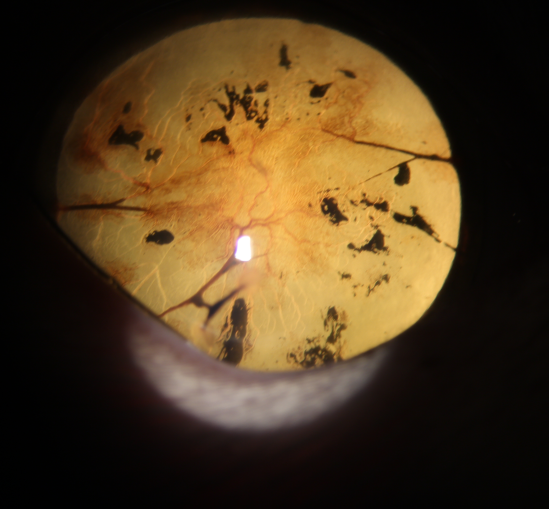

이미 녹내장으로 인해 눈의 상태가 좋지 않아 눈 속의 혈관 형성과 함께 유리체 변성이 매우 심했고, 검안경 검사에서 망막 위축도 심한 상태였습니다.

처음에는 제 친구도 녹내장 안약에 효과가 있어 안압이 떨어지는 듯하더니 한 달쯤 지났을 때는 다시 안압이 60도까지 오른 상태에서 내원해 주셨어요.▲시도포비아주사= 녹내장약의 횟수도 증량해보고 종류도 바꿔보았지만 효과가 없고, 이미 시력이 소실된 상태이므로 안로주사로 알려진 cido for vir 시도포비아주사를 맞기로 했습니다.